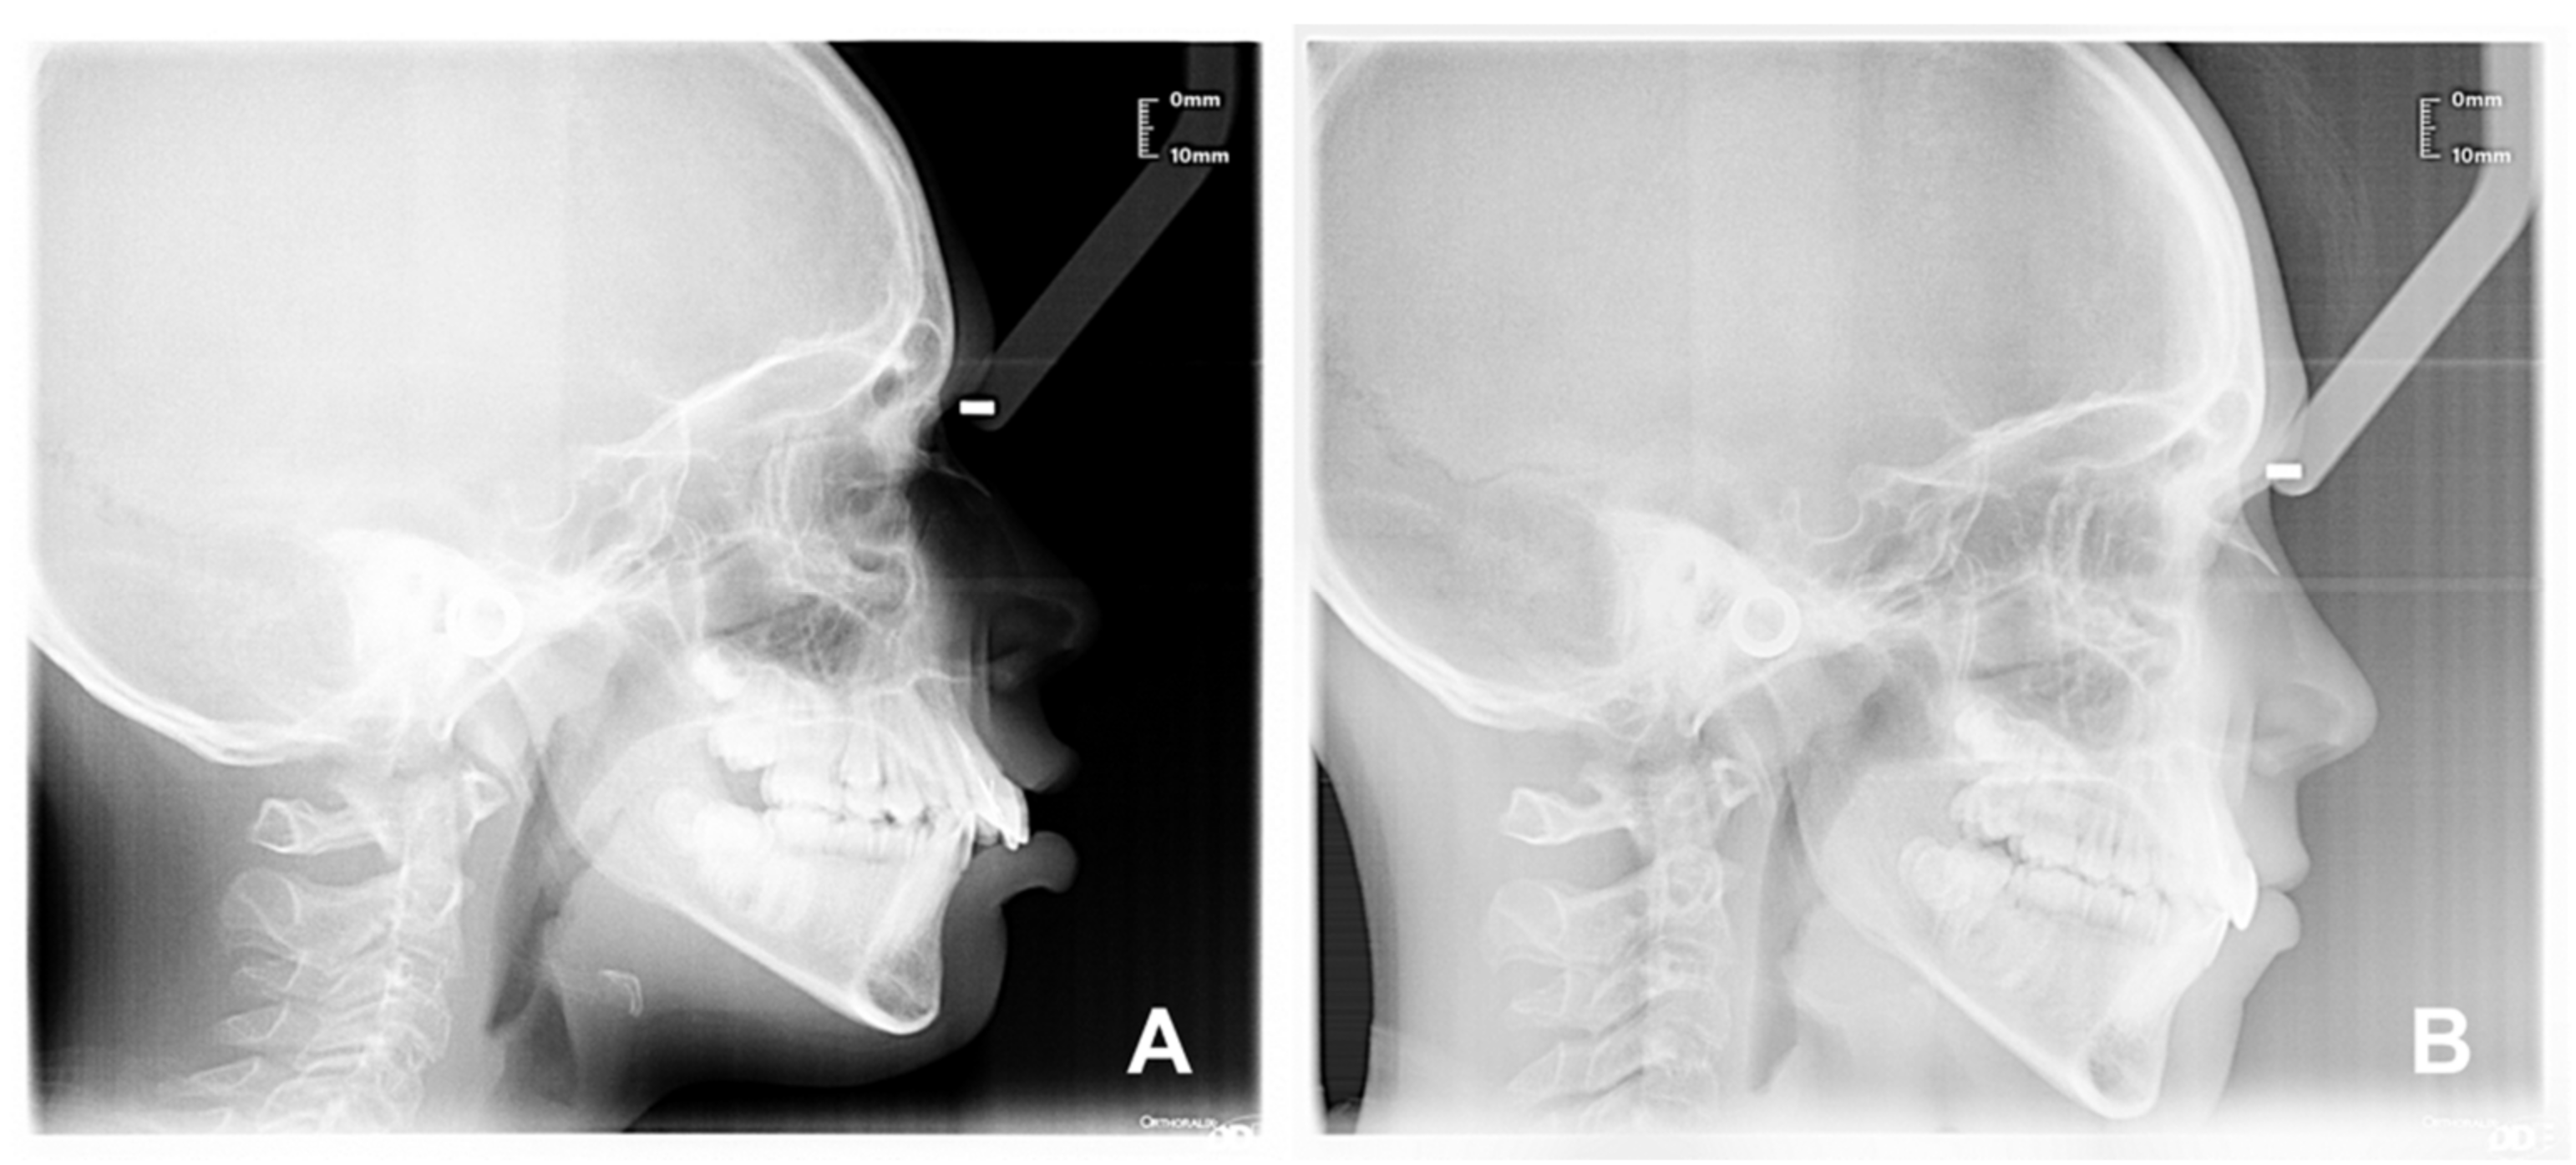

| Sagittal plane analysis: SNA (angle comprised between Sella–Nasion and Nasion point A segments) SNB (angle comprised between Sella–Nasion and Nasion point B segments) ANB (angle comprised between Nasion point A and Nasion point B segments) Vertical plane analysis: Sna-Snp^Go-Gn (intermaxillary angle, angle comprised between the bispinal plane and the mandibular plane) S-N^Go-Gn (mandibular angle, angle comprised between the Sella–Nasion segment and the mandibular plane) PFH/AFH (posterior facial height and anterior facial height ratio) Growth predictors: N-S-Ar (saddle angle comprised between Nasion–Sella and Sella–Articular segments) S-Ar-Go (articular angle comprised between Sella–Articular and Articular–Gonion segments) Ar-Go-Me (gonial angle comprised between Articular–Gonion and Gonion–Menton segments) Ar-Go-N (upper gonial angle comprised between Articular–Gonion and Gonion–Nasion segments) N-Go-Me (lower gonial angle comprised between Nasion–Gonion and Gonion–Menton) Dental analysis: Is:NA (maxillary incisor distance) Ii:NB (mandibular incisor distance) OVJ (overjet) OVB (overbite) IsIi: interincisal angle (angle between the major axis of the upper and lower incisors). Upper airway space analysis: SPAS: superior posterior airway space (distance between the soft palate and the posterior wall of the nasopharynx measured along a line parallel to Gonion–Menton (Go–Me) plane) MAS: medium airway space (distance between the lower tip of the soft palate and the posterior wall of the oropharynx measured on a line parallel to Go–Me plane) IAS Inferior Airway Space (distance between the lingual base along the mandibular Go-Me plane and the posterior wall of the pharynx) Mandible measurements Ar-Go (ramus height measured on Articular-Gonion segment) Go-Me (corpus length measured on Gonion-Menton) |